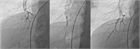

1. 専門施設あるいはコンサルトすることで、多職種による治療方針の検討を行い、肺血栓内膜摘除術(PEA)(中枢)、バルーン肺動脈形成術(BPA)(末梢)、肺血管拡張薬(細動脈)の組み合わせによる集学的治療を行う。

1. 手術の適応とならないまたはPEA後残存、再発したCTEPHに対してBPAを行うが、BPA前に、リオシグアトやセレキシパグを投与してもよい。